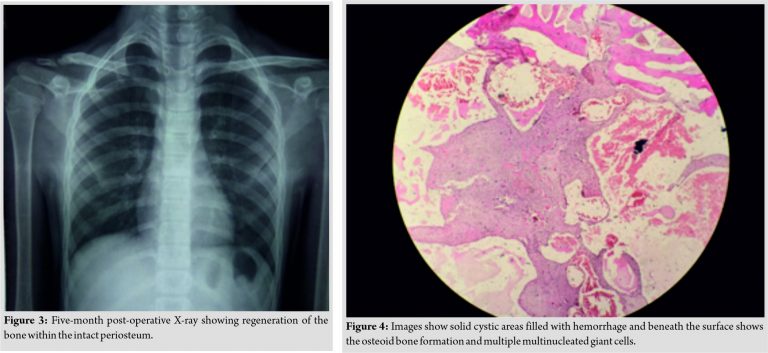

The term aneurysmal bone cyst was first given by Jaffe and Lichtenstein while describing its radiological features in 1942 [8]. Aneurysmal bone cyst occurring in this age group is common but not so much in the clavicle [2]. Rarer are the occurrences of this tumor in the rib, skull, and mandible. The occurrence of the lesion seems to be rarer in the medial third which has been reported [9]. Aneurysmal bone cyst can also be found in association with other lesions such as giant cell tumor, chondroblastoma, osteoblastoma, fibrous dysplasia, nonossifying fibroma, and chondromyxoid fibroma [10,11,12]. Patients usually present with pain, swelling around the lesion, and sometimes coinciding history of trauma. These tumors can be treated by extended curettage, marginal resection, arterial embolization, and rarely low dose radiation [10]. Furthermore, cases have been treated with bisphosphonates in areas where it is unresectable or for recurrences [13,14]. Our case was treated by marginal resection. On regular follow-up,the regeneration of the bone within the intact periosteum can be seen (Fig. 3).

Aneurysmal bone cyst occurring in this age group in the clavicle is a rare presentation which requires mention in literature. Our case was treated by marginal resection. On regular follow-up,the regeneration of the bone within the intact periosteum can be seen (Fig. 4).